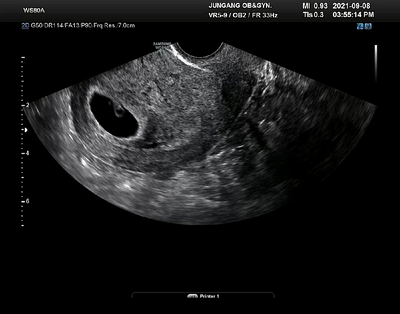

튼튼이는 2022년 4월 20일 08시 42분 태어났어요~ (튼튼이는 여아예요^^;) 시흥시 중앙 산부인과에서 2.76...